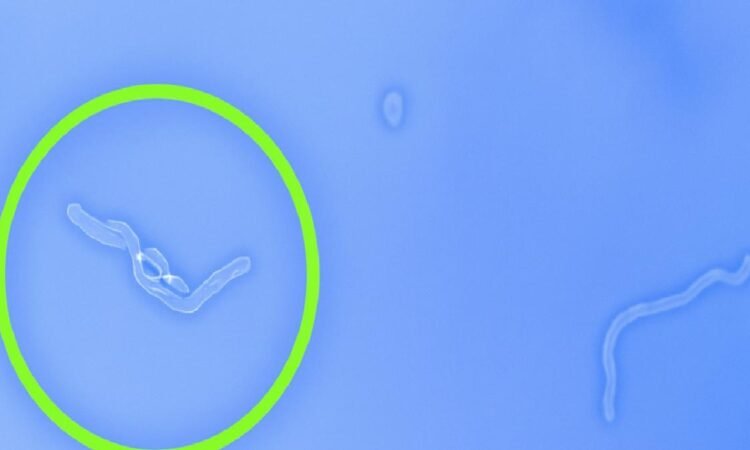

Bir noktaya bakarken ya da parlak bir zemine gözünüzü çevirdiğinizde havada süzülen küçük, yarı saydam iplikler ya da lekeler görüyorsanız, yalnız değilsiniz. Tıp literatüründe “floaters” olarak bilinen bu uçuşan cisimler, göz içindeki jel kıvamındaki vitreus sıvısında meydana gelen küçük değişimlerden kaynaklanıyor.

Çoğu uçuşan cisim, gözünüzün hareketiyle birlikte yer değiştirir ve kısa süre sonra fark edilmez hale gelir. Panik yapmak yerine, gözlerinizi bir süre dinlendirmek bu etkiyi azaltabilir.

Yukarı-aşağı veya sağa-sola doğru hızlı ama kontrollü göz hareketleri, vitreus içindeki bu parçacıkların yer değiştirmesini sağlar. Böylece görüş alanınızdaki bulanıklık geçici olarak azalabilir.